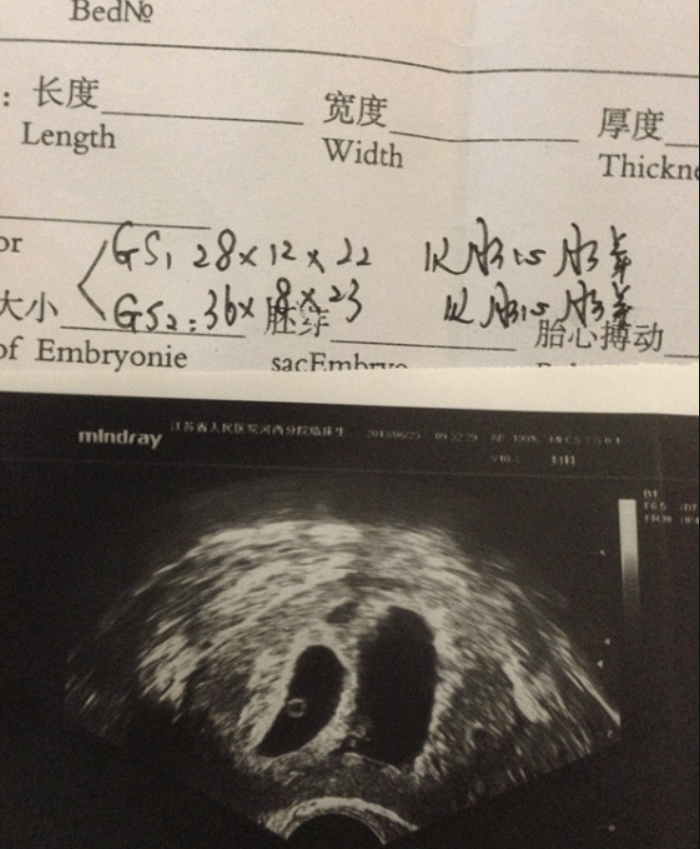

我有嚴重的多囊卵巢綜合徵,頑固排卵障礙,在本地醫院促排多次都未果,後來第一次做了ivm,懷上但是胚停了,清宮。第二次促排,配了15個,但因為過度刺激,又等了4個多月。下面就來具體說一下在廣東醫附院做凍胚試管的經歷。凍胚好孕了2013.5.25在廣東醫附院移植兩枚凍胚。6.4晨尿大衛和秀兒都測到了6.8官方驗血,HCG值大於1000。護士很大聲的報我的HCG值和說我懷孕了,搞得旁邊的大姑大媽都跑來問...